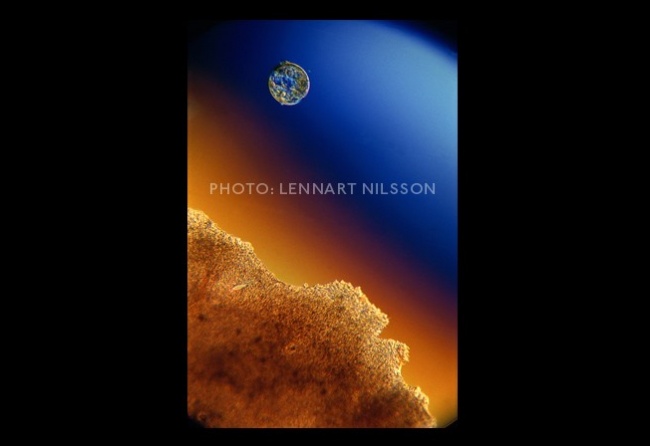

6 A week later, the embryo migrates to the womb by floating downwards through the fallopian tube